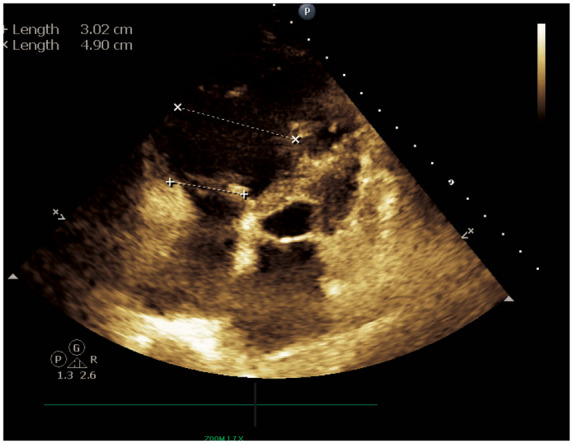

Transthoracic echocardiogram obtained in the ICU confirmed severe right ventricular dilatation with moderate pulmonary hypertension (Figure 4). Thrombus measuring 1.3 cm × 1.3 cm was appreciated in the right ventricle (Figure 5), with an echodensity present on the anterior tricuspid leaflet which was felt to represent thrombus (Supplementary material online, Video S1). Additionally, a thrombus measuring 1.4 cm × 1.9 cm was visualized in the dilated inferior vena cava (2.50 cm) (Figure 6). On day 4 of admission, the patient tested positive for the COVID-19 virus via nasopharyngeal swab polymerase chain reaction (PCR).

Figure 4.

Apical four-chamber echocardiographic view with right ventricular linear measurements displayed. Qualitatively, a severely dilated right ventricle is represented. Quantitatively, right ventricular size is increased by linear measurement of the chamber’s mid cavity (4.90 cm).